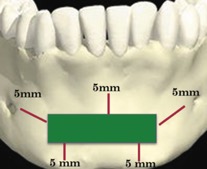

В 1992 году Misch для профилактики осложнений при получении костного блока из подбородочной области предложил правило «трёх пятёрок», при котором выделяется зона безопасности на 5 мм апикальнее от верхушек корней зубов (профилактика чувствительности зубов), на 5 мм медиальнее от ментальных отверстий (профилактика парестезии) и на 5 мм к верху от нижнего края нижней челюсти (профилактика перелома) [3] (Рис. 2).

Рисунок 2. «Правило трёх пятеёрок»